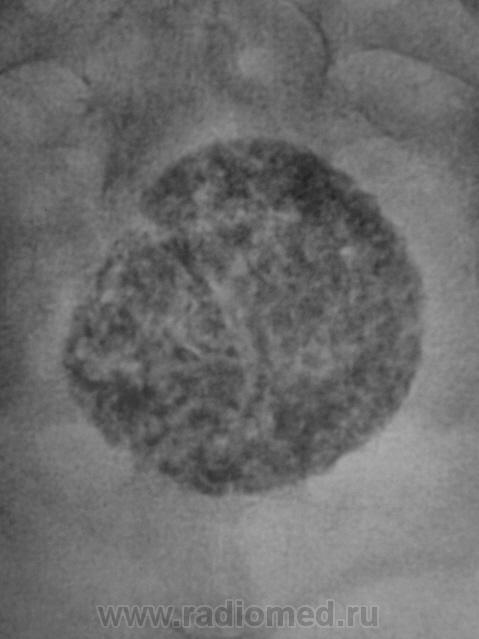

Пациентка направлена на рентгенографию тазобедренного сустава по поводу "артроза". Беспокоят вроде-бы боли в области правого тазобедренного сустава. Произведена рентгенография в прямой стандартной проекции. Рентгенологических данных за артроз не было. Но по краю пленки что-то "маячило". Пациентке 56 лет.

Досняли... Ваше мнение уважаемые коллеги?

Или конкремент мочевого пузыря или фиброматозный узел с обызвествлением. Если в больнице есть УЗИ.... нет - экскреторная, до нее можно латерограмму, пневмоцистограмму и т.п.

Добрый вечер, Валентин Львович! Представленный Вами случай - обызвествление миомы матки, раза три наблюдал. Неплохо бы боковую проекцию, вдруг хондрома крестца.

Вообще-то весьма характерная картина фибромиомы матки, осмотра гинеколога и УЗИ вполне достаточно

Согласен, и даже без каких-либо минимальных возражений